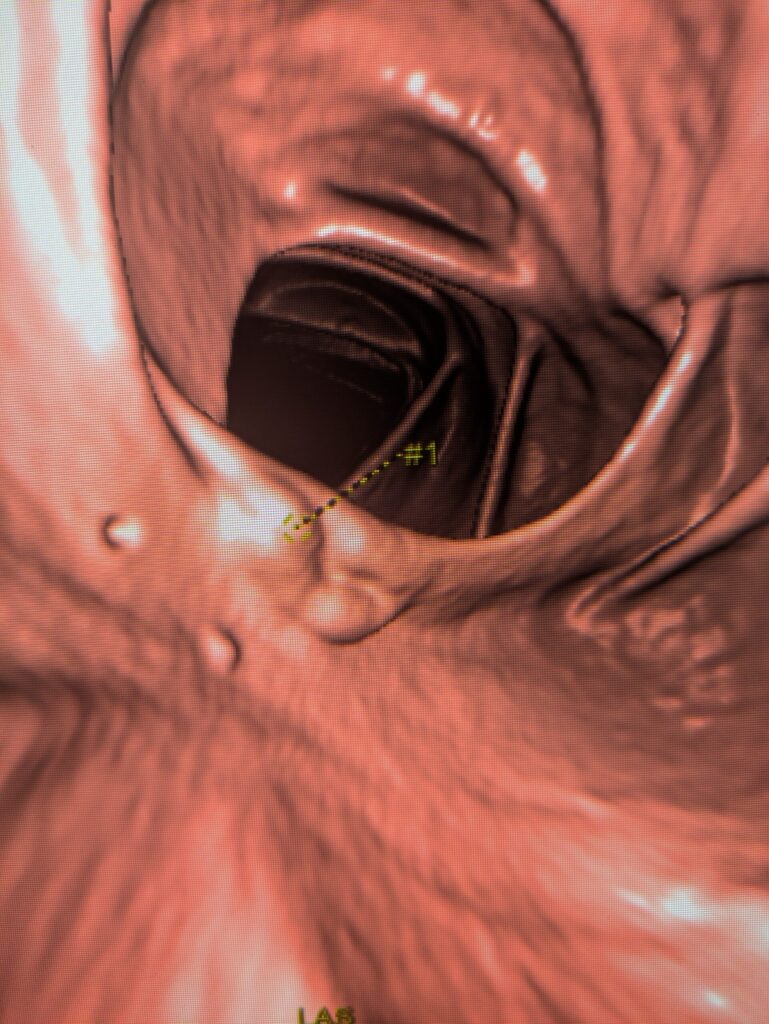

CTC uses CT scanning to create 3D images of the colon, allowing doctors to “virtually” inspect the inside without inserting a scope.

4. 3D images and maps are generated with software.